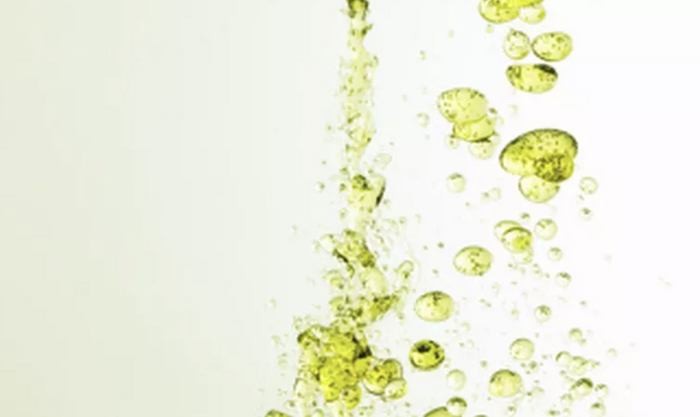

Интенсивность сигнала поменялась из-за того, что физ.раствор частично смешался с силиконом, и вследствие этого определяются пузырьки физ.раствора в силиконе - т.н. признак "салатного масла" или "salad oil sign" (капли, как при добавлении масла в воду):

которые я отметил красными стрелочками:

и на секвенции с подавлением воды, которая становится на картинке "чёрной" (синяя звёздочка), а силикон остаётся "белым" (красная звёздочка):